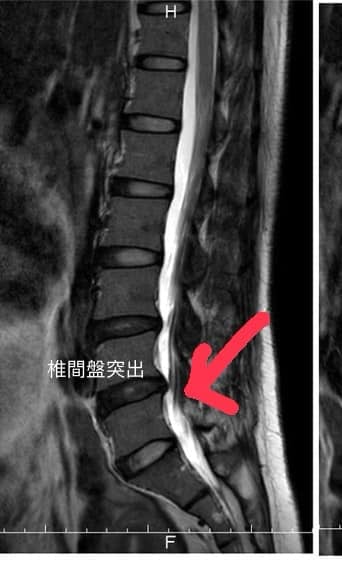

⭕️這是個難忘的醫案,四十多歲的越南阮小姐在門診中詢問我,她的腰椎已經痛了快半年 ,後從十一月到一月十二號就醫這兩個月,每天都是必須吃高劑量止痛藥才免強可以走路,醫院安排的核磁共振明顯看到L4/L5椎間盤突出,導致他左腿整支麻痛跟電到的感覺,左腰非常痠痛,稍微咳嗽跟大聲說話整個腰會被電到,非常典型的坐骨神經痛壓迫,這次由台灣的企業主老闆介紹來門診就醫

💢評估:還沒出現馬尾症候群症狀,沒有大小便失禁,約定治療三周如果有改善就繼續治療,如果沒改善強烈建議回原本醫院接受神外醫師開刀